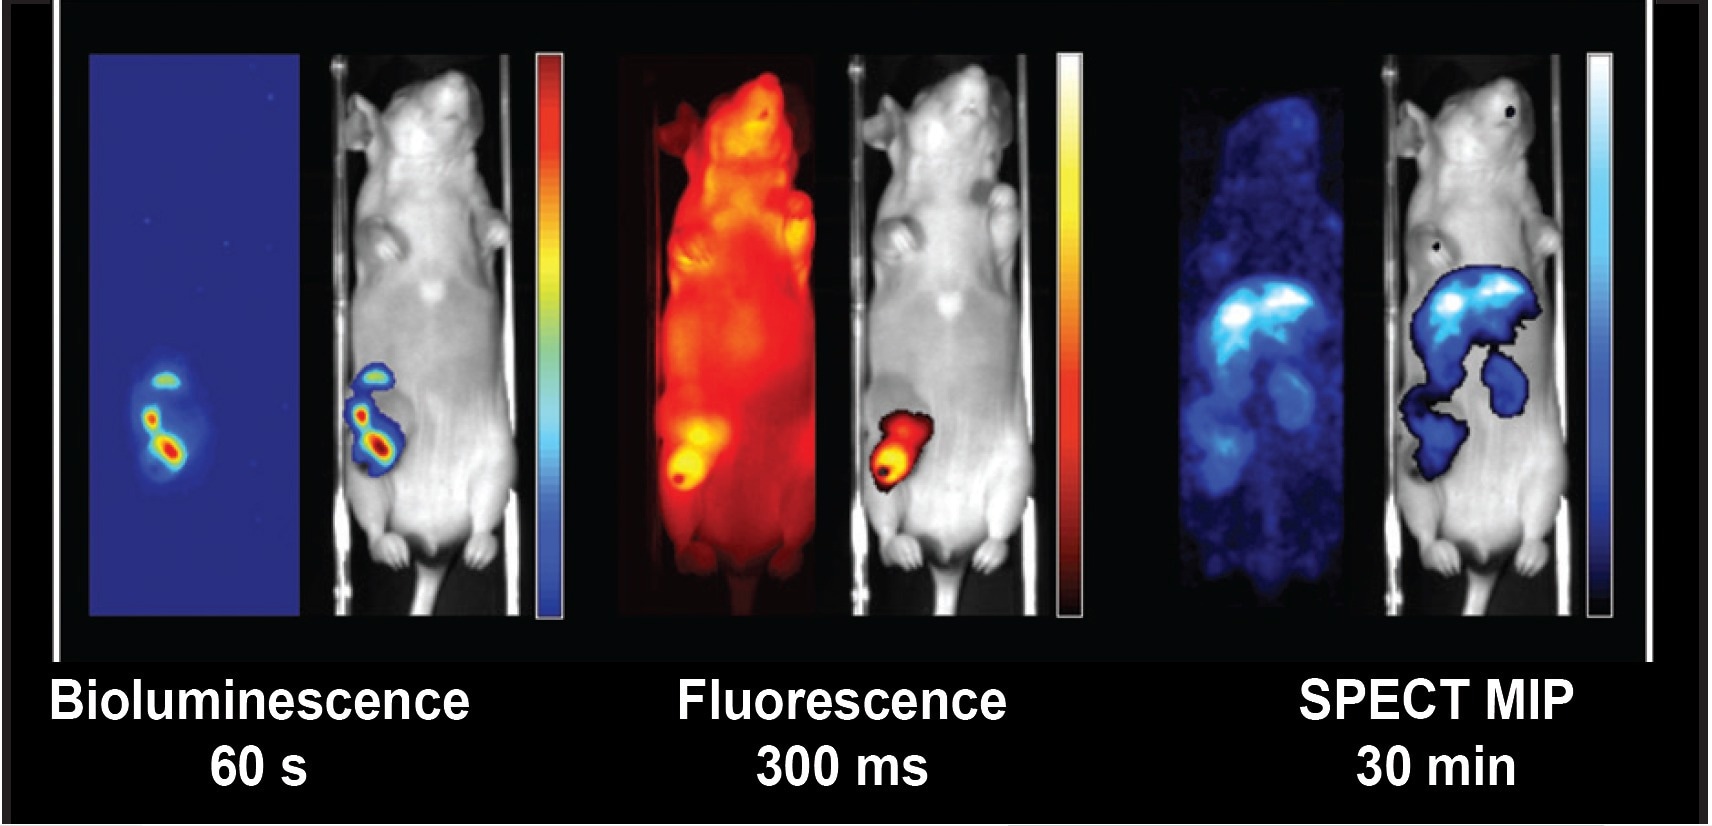

Figure 2. Example of complementary registered bioluminescent, fluorescent, and nuclear images in one scanning session with a single dose of anesthesia [Multimodality Molecular Imaging of Lung Disease Using PET, CT and Optical Imaging, SSG07-09 Oral Presentation, RSNA 2019].

Figure 2. Example of complementary registered bioluminescent, fluorescent, and nuclear images in one scanning session with a single dose of anesthesia [Multimodality Molecular Imaging of Lung Disease Using PET, CT and Optical Imaging, SSG07-09 Oral Presentation, RSNA 2019].

Translation of optical imaging results to clinically compatible PET or SPECT data is easily accomplished by adding the desired nuclear modality to the OI/CT system. MILabs can offer any combination of in-line PET, SPECT, optical, and CT on a single platform. These modalities can be added at any time to suit your requirements and budget. This makes one-to-one translation from basic optical research data to clinically compatible nuclear imaging technologies possible and avoids animal shuttling with inconsistent anesthesia conditions and image registration challenges.